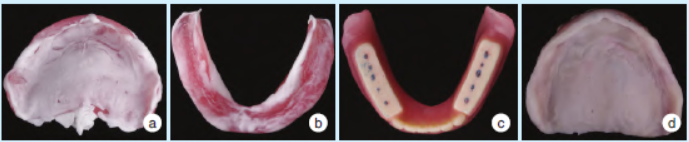

治疗性义齿戴入及咬合与黏膜组织的调整。①贴合指示剂检查义齿组织面与边缘,调磨缓冲压力过大的区域;②调整咬合使后牙达到均匀的咬合接触;③均匀去除义齿组织面约1mm,将组织调理剂均匀衬垫于义齿组织面;④最后再一次检查咬合。治疗性义齿戴入后,嘱患者每一周或两周复诊进行咬合调整和组织调理(图1)。

图1 治疗性义齿初戴检查及调整

拟合治疗前后扫描的义齿组织面形态,其差异反映了治疗前后的义齿空间变化量。义齿空间变化随治疗性义齿的戴用表现出的规律为下颌颊棚区的扩展,下颌舌骨区的适应性变化以及唇侧基托的扩展(图2)。

图2 义齿形态扫描所示治疗前后下颌义齿空间变化

2.2义齿组织面、咬合印迹、哥特式弓描记图像和黏膜状态变化

治疗性义齿组织面呈现的变化规律:组织调理剂逐渐分布均匀,下颌义齿唇颊侧边缘向外扩展,舌侧适应性变化(图3)。咬合印迹变化:逐渐对称、均匀,呈明确的点接触,无早接触,无滑动(图4)。

图3 治疗前后义齿组织面变化